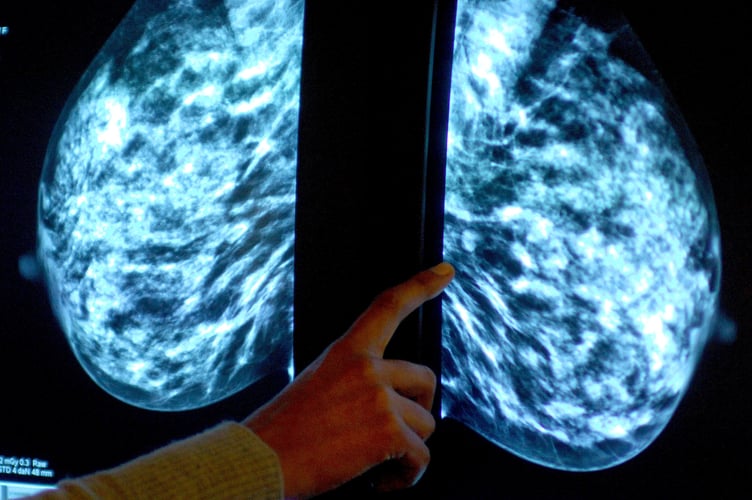

Breast screening uptake in Devon remains below pre-pandemic levels, new figures show.

It comes as charities have said women still face too many barriers to regular testing, as fewer people in England underwent tests than before the coronavirus pandemic